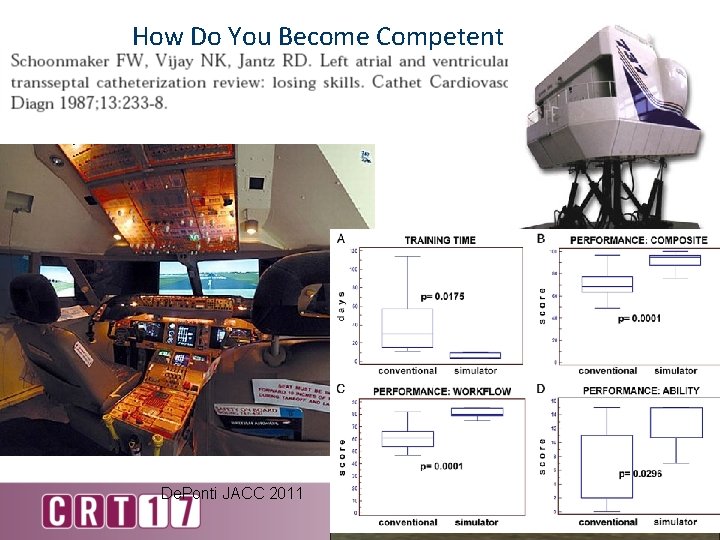

How Do You Become Competent De. Ponti JACC 2011